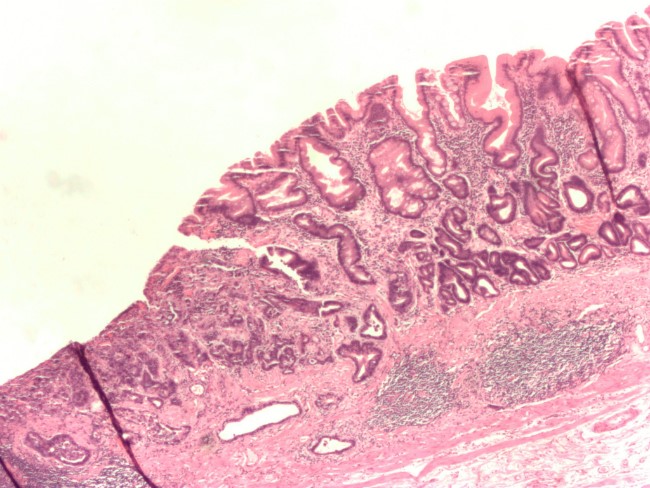

На начальном этапе заболевания раковые образования возникают из эпителия и углублений слизистой оболочки, а также из плотных железистых тканей. По мере развития недуга опухоль прорастает в соседние органы.

Обычно опухоль появляется в сосочковой области. В медицине он именуется перипапиллярным раком. Супрапапиллярные раковые образования, то есть те, что образуются в верхнем отделе тонкого кишечника, встречаются лишь у 16% больных. Реже можно обнаружить инфрапапиллярный рак, когда раковое образование расположено в нижней горизонтальной области 12-перстной кишки.

Пациент в обязательном порядке проходит ультразвуковое исследование органа. Оно определяет поверхностное изменение слизистого эпителия кишечника. Сдаются анализы крови, кала и мочи.